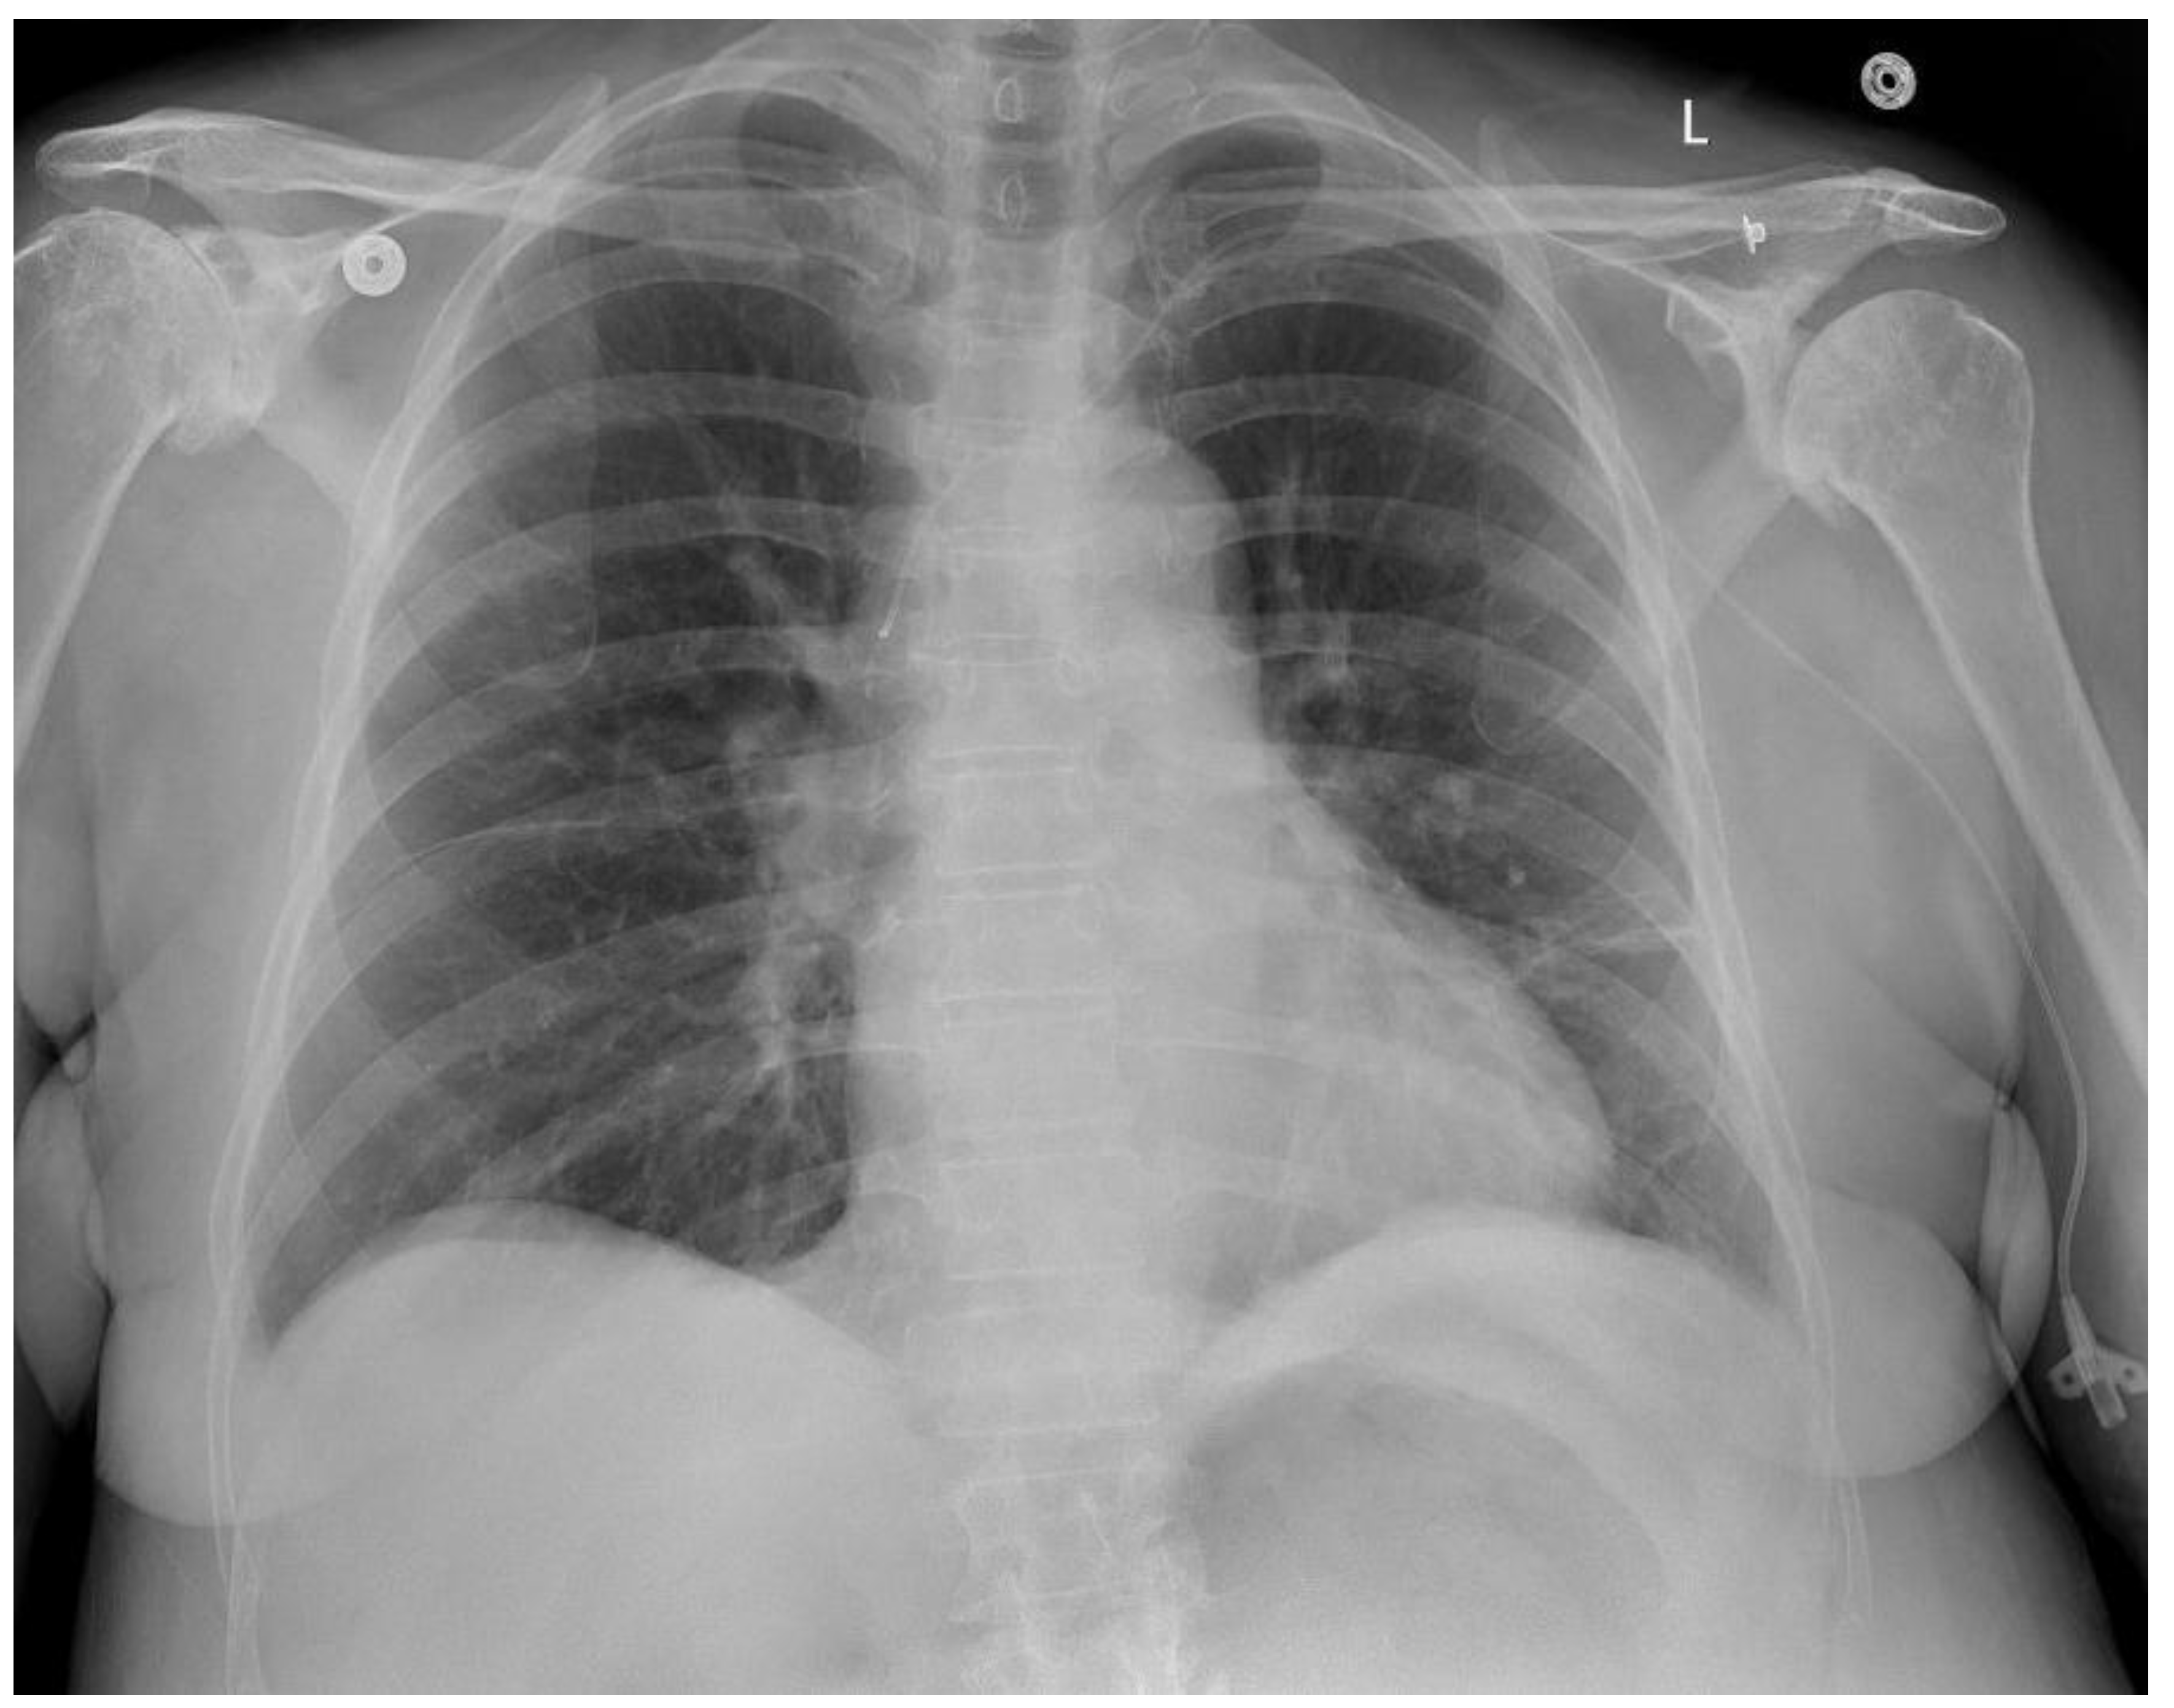

During hospitalization, laboratory and imaging studies played a key role in evaluating suspected vancomycin-induced DRESS syndrome. Blood tests showed dynamic changes in white blood cells, eosinophils, lymphocytes, and neutrophils, supporting an evolving hypersensitivity reaction. Mild liver involvement was noted, while renal function remained stable. Imaging was limited to a chest X-ray, which ruled out acute cardiopulmonary issues but noted chronic musculoskeletal changes and borderline cardiac enlargement. The absence of a skin biopsy and broader diagnostic tests limited definitive confirmation. Overall, investigations were crucial for monitoring organ function and guiding treatment, despite certain diagnostic limitations.

Image 3.

Preprints 162860 g001